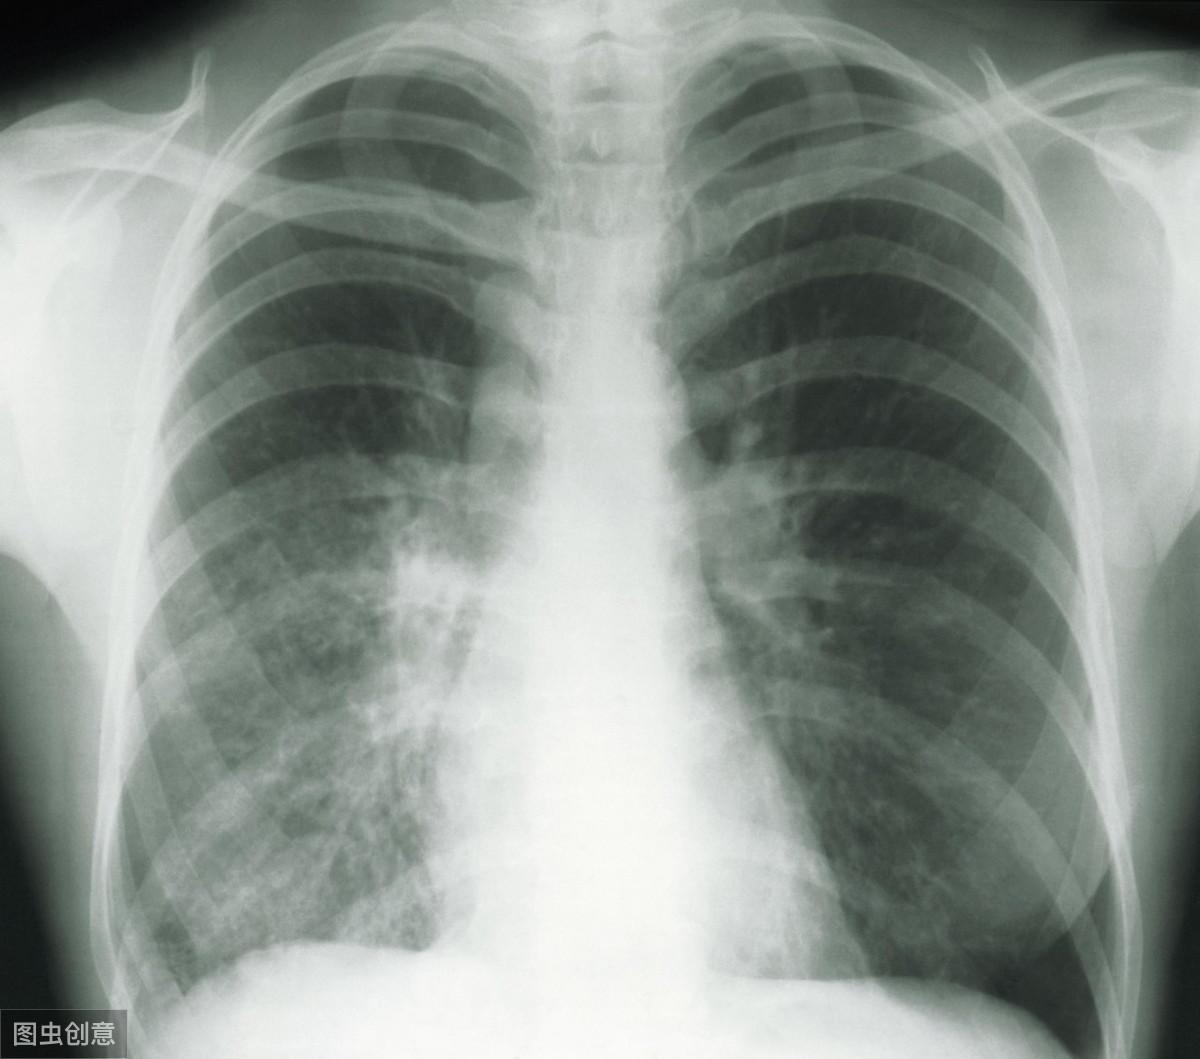

直到去医院拍了片子才知道问题的严重性,和两年前的肺部CT一对比,肺部结节已经癌变,变成了肺癌!因为肺部积水,右肺已经完全消失不见了,最后从肺部抽出了5560毫升水,肺部结节也很多,最后诊断为肺癌、骨转移癌与胸腔积液。